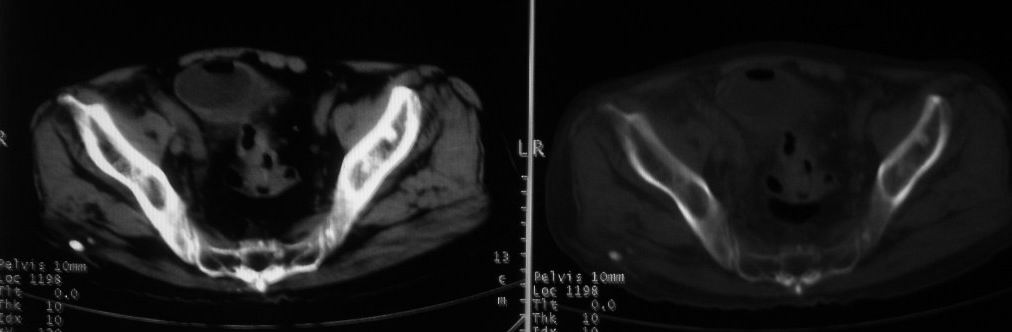

以下是引用深泽交通医院在2008-10-3 15:33:00的发言:[br]前列腺实性增大伴分叶状,与包膜间隙境界不清;椎体松质区间结节样密度影,考虑:前列腺癌,并椎体成骨性转移